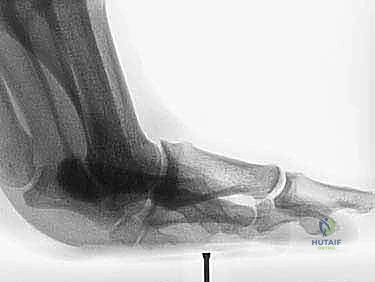

2. التصوير بالأشعة السينية (X-Rays)

يتم إجراء صور أشعة سينية بوضعيات تحمل الوزن (Weight-bearing) وبوضعيات الإجهاد (Stress views). تساعد الأشعة السينية في:

* استبعاد وجود كسور في عظام المشط أو السلاميات.

* تقييم العظام السمسمانية (البحث عن كسور أو هجرة غير طبيعية للعظام السمسمانية، مما يدل على تمزق الصفيحة).

* تقييم تضيق المسافة المفصلية.